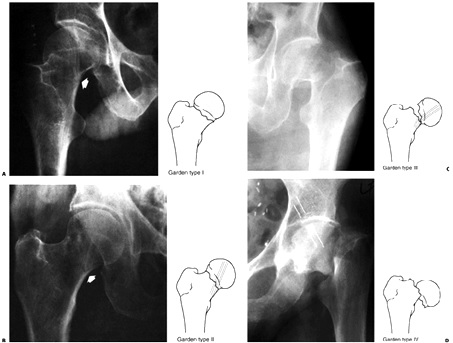

3- تقسيمبندي بر اساس جابجايي شكستگي (تقسيمبندي گاردن)

اساس تقسيمبندي گاردن ميزان جابجايي شكستگي در راديوگرافي AP پروگزيمال فمور است.

گاردن تيپ I : شكستگي در هم فرو رفته (Impacted) و ناكامل است و ترابكولهاي استخواني تحتاني گردن دست نخورده باقيمانده است.

گاردن تيپ II : شكستگي كامل اما بدون جابجايي است و ترابكولهاي استخواني تحتاني گردن توسط خط شكستگي بهم خورده است.

گاردن تيپ III : شكستگي كامل با جابجايي ناكامل است. در اين شكستگي كوتاهي و اكسترنال روتيشن قطعه ديستال رخ مي دهد. در اين نوع شكستگي تداوم ترابكولهاي استخواني سرفمور با استالوبوم بهم خورده است.

گاردن تيپ IV : شكستگي كامل با جابجايي كامل قطعات نسبت به هم است. اما تداوم ترابكولهاي سرفمور با استابولوم حالت نرمال خود را خواهد داشت .

نقسيمبندي گاردن:

تيپ I ) شكستگي ناكامل، در هم فرو رفته و زاويه گردن در والگوس قرار دارد.تيپ II شكستگي كامل اما بدون جابجايي است.